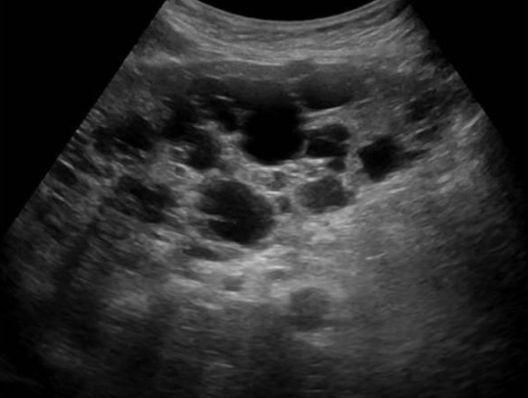

2D US: bilateral cortical/medullary cysts, varying sizes, simple/hemorrhagic, enlarged bilateral kidneys, normal tissue replaced with cysts,

ADPKD (Autosomal Dominant Polycystic Kidney Disease ) → most common hereditary kidney disorder

clinical hx: 30 y/o develops, associated with polycystic liver disease

s/sx: HTN, palpable masses, swollen abdomen, pain w/ rupture, bouts with kidney stones